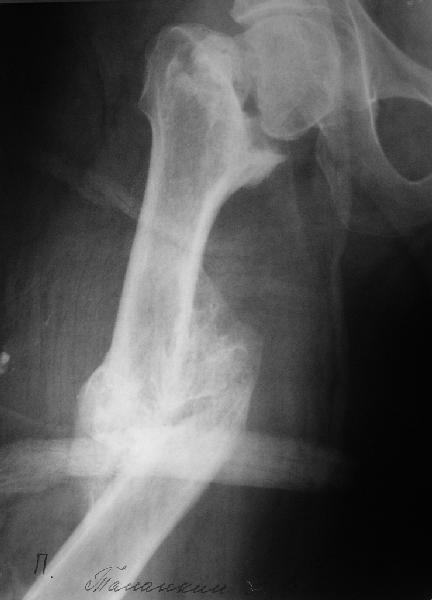

It appears to me that the neck femur and shaft femur are old injuries. I would give preference to the distal femur fracture, but you can only align

the shaft if the malunited midshaft femur fracture is corrected. So my plan:

1. Open reduction and plating of the midshaft femur fracture

2. Distal femur fracture reduction and fixation by indirect reduction if possible, direct reduction if required. I would use locking plate if possible, if not distal femur plate.

Больной поступил в клинику. Дополнительные сведения: диафизарный перелом (открытый)получил 5 лет назад - падение с 5 этажа. Лечился консервативно. Через год стал ходить без трости, хромоты не было, колено гнулось ( со слов больного),В принципе был удовлетворен своим состоянием. 1,5 месяца назад упал в подъезде (в состоянии алкогольного опьянения). Отказался от 2 группы инвалидности - просто не пошел на переосвидетельствование. Живет с мамой (пенсионерка).